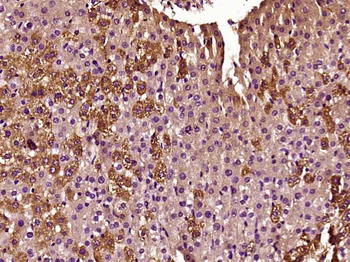

IDH2 Rabbit Polyclonal Antibody

FC, IF, IHC-Fr, IHC-P

应用稀释比例:IHC-P=1:100-500, IHC-F=1:100-500, IF=1:100-500, Flow-Cyt=0.2ug/test